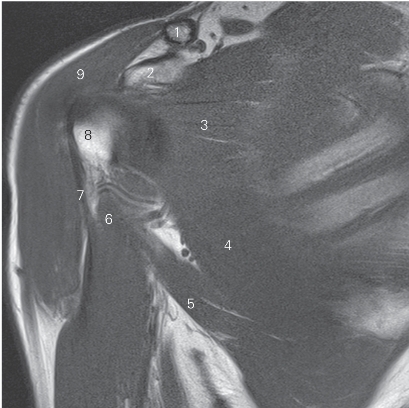

图4-21 经肩锁关节的矢状断层MR T2WI FS

1 锁骨 clavicle 2 肩锁关节 acromioclavicular joint

3 肩峰 acromion 4 冈下肌 infraspinatus

5 肱骨头 head of humerus 6 三角肌 deltoid

7 小圆肌 teres minor

8 腋神经及旋肱后动脉 axillary nerve and posterior humeral circumflex artery

9 肱三头肌 triceps brachii 10 大圆肌 teres major

11 胸大肌 pectoralis major 12 喙肱肌 coracobrachialis

13 肩胛下肌 subscapularis 14 喙突 coracoid process

15 肩袖间隙 rotator interval 16 冈上肌 supraspinatus

17 喙肩韧带 coracoacromial ligament